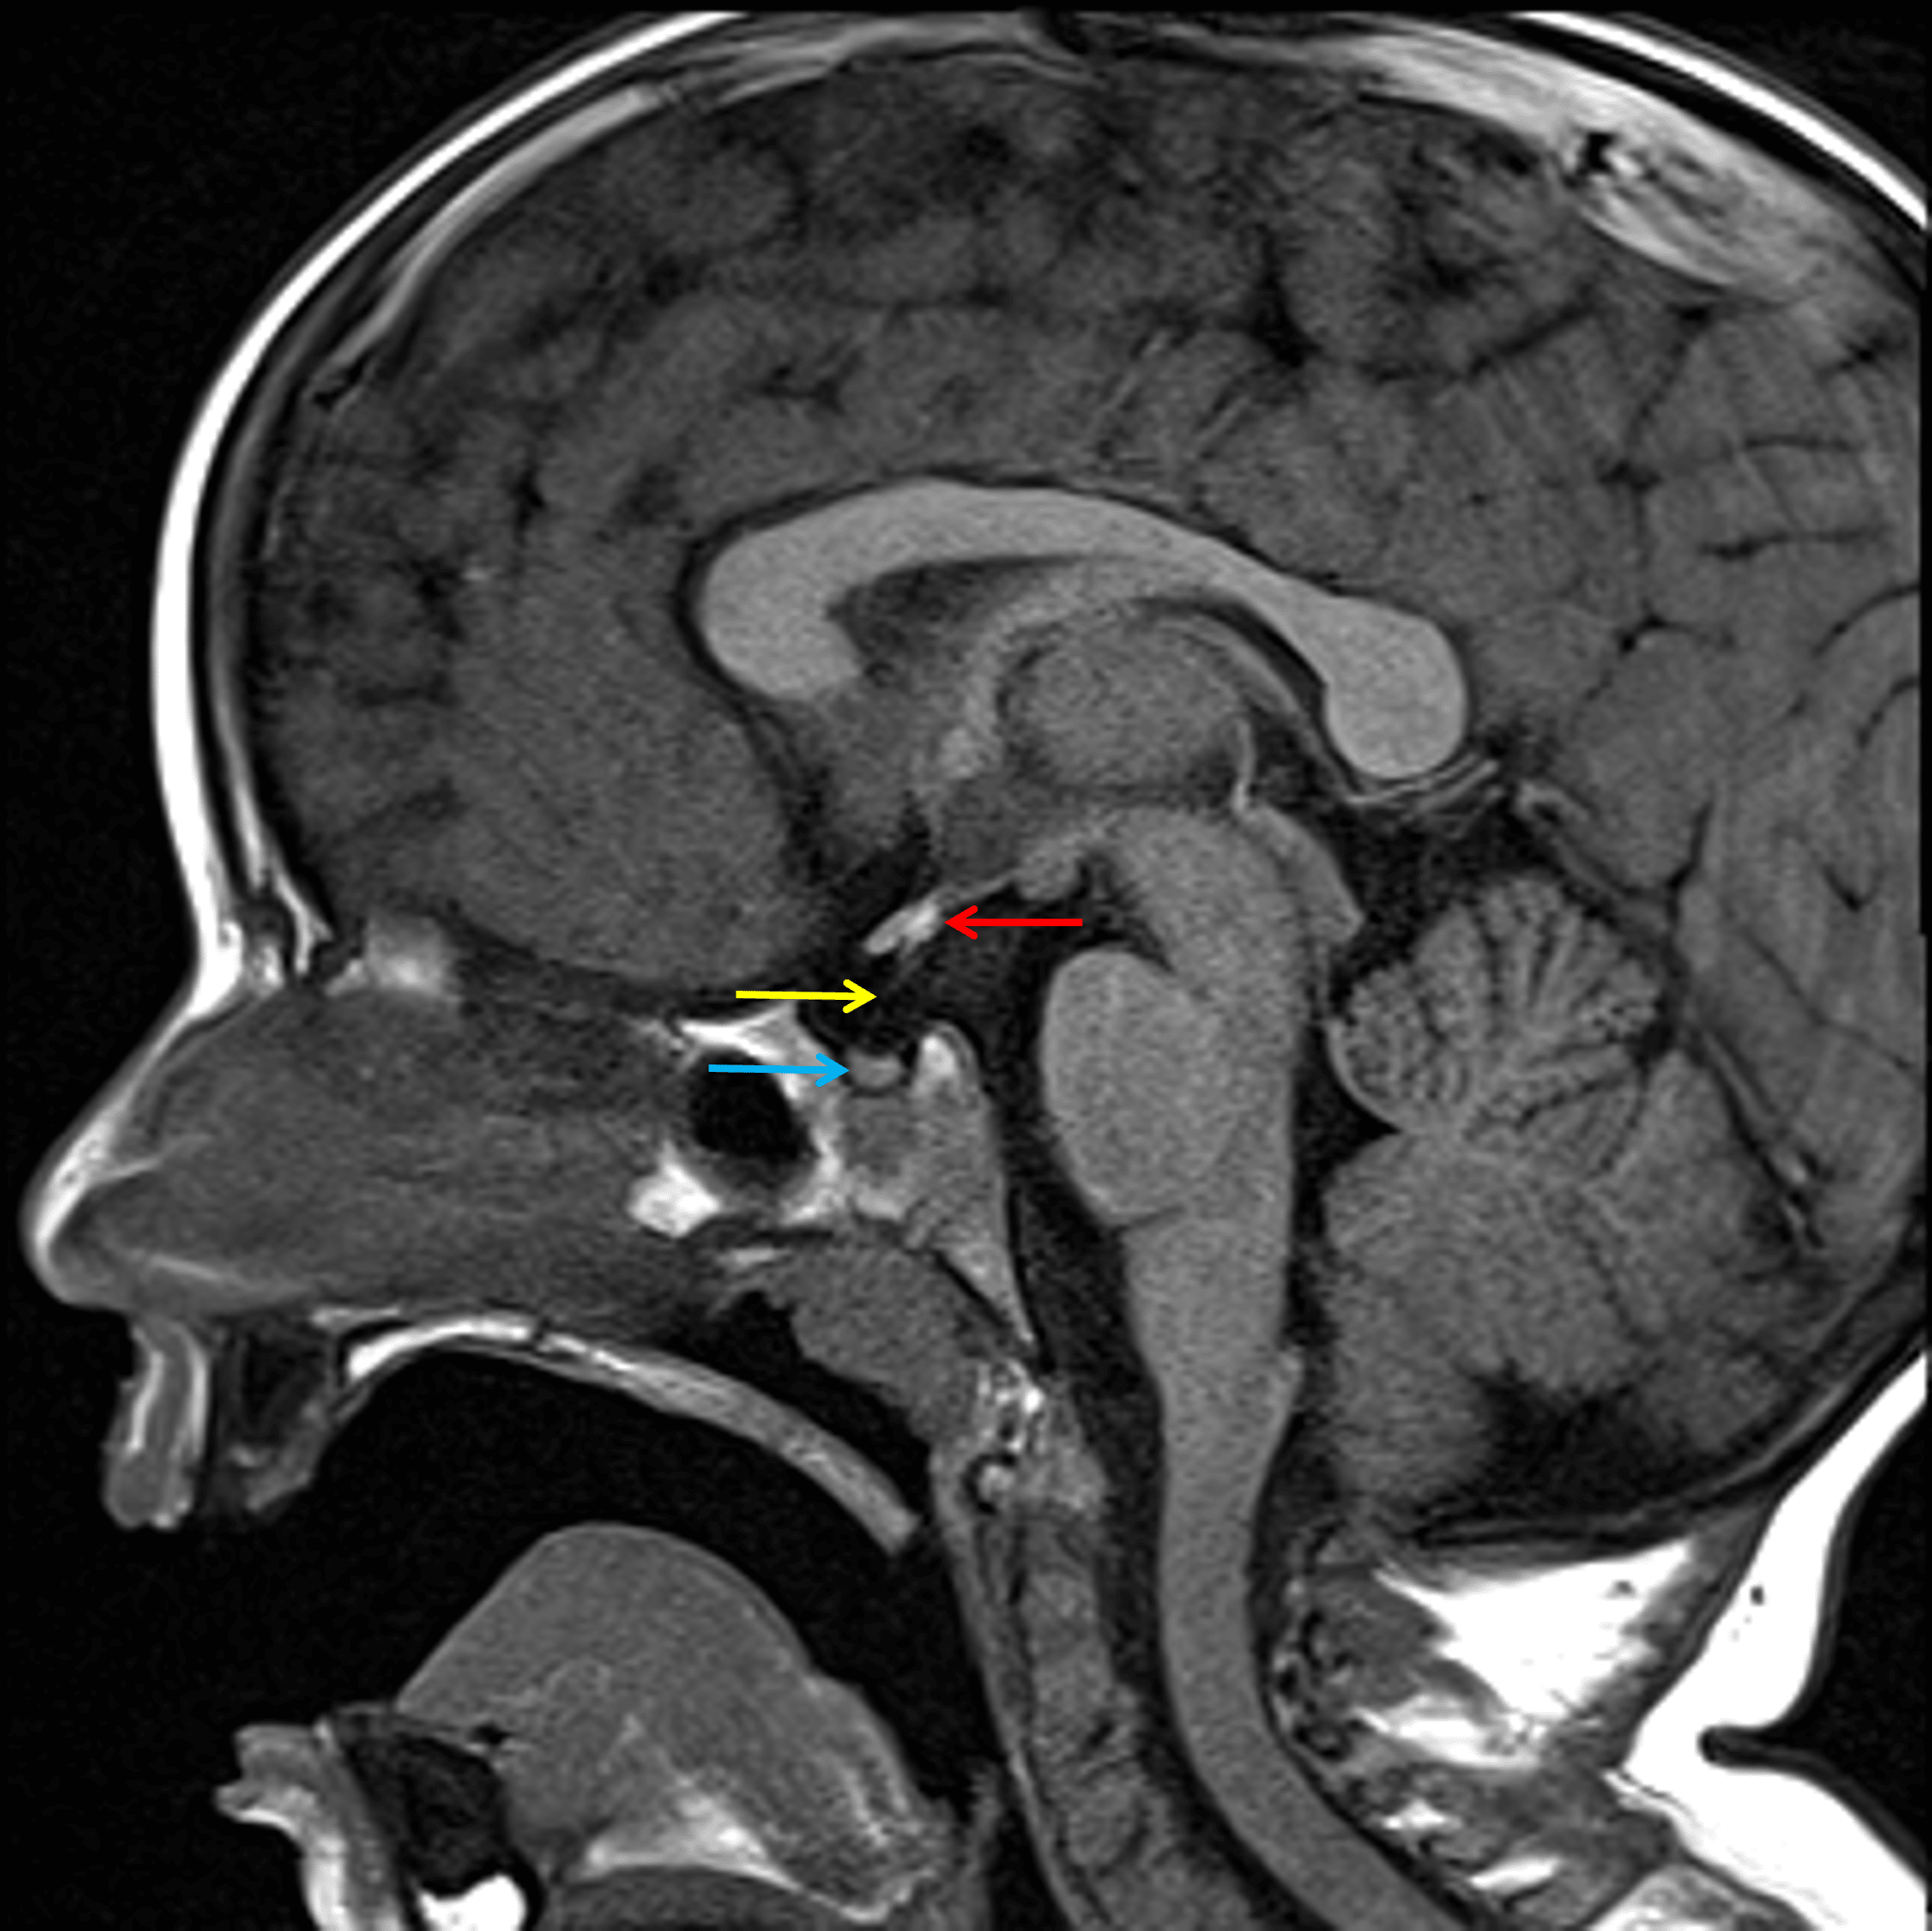

• Ectopic posterior pituitary gland, which lies at the base of the pituitary stalk

• Hypoplastic appearance of the pituitary stalk and possibly also of the adenohypophysis

• No pituitary mass

Ectopic posterior pituitary at the base of the pituitary stalk (red arrow) with hypoplastic appearance of the pituitary stalk (yellow arrow) and possibly also of the adenohypophysis (blue arrow).